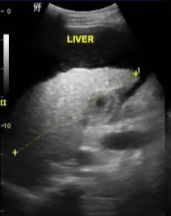

What is the classic sonographic hallmark of hepatic steatosis?

Increased echogenicity with decreased penetration and poor visualization of vessels/diaphragm.

Diffuse fatty liver (increased echogenicity and attenuation, poor visualization of diaphragm and vasculature)